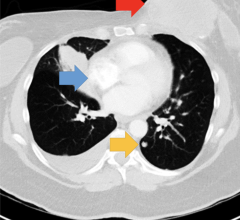

This video shows a computed tomography (CT) scroll through showing bowel ischemia and perforation (see arrows) due to …